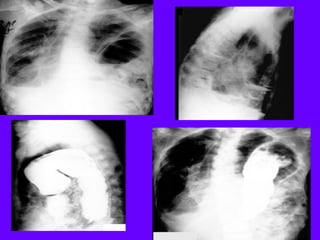

SquamousCell Carcinoma

Anterior segment of LUL

Thick wall

Fluid level

Full hilum

SquamousCell Carcinoma Lung

Irregular lumen

left hilar LN